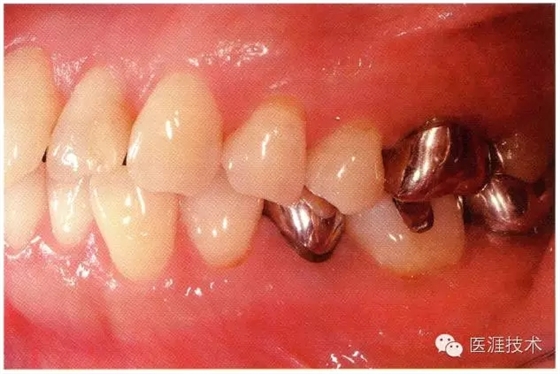

65歲男性的健康口腔內(nèi)部

65歲男性。糖尿病與高血壓病史,目前治療中,40歲左右戒煙。有唾液減少傾向,但目前尚未見對牙齒及牙周組織的影響。初診時齲齒治療后,來院就診保養(yǎng)10年,雖因刷牙過度有牙齦萎縮,但牙齒及牙周組織仍保健康。如可妥善維持菌斑控制,則可維持牙周組織健康,不會減少牙周組織。